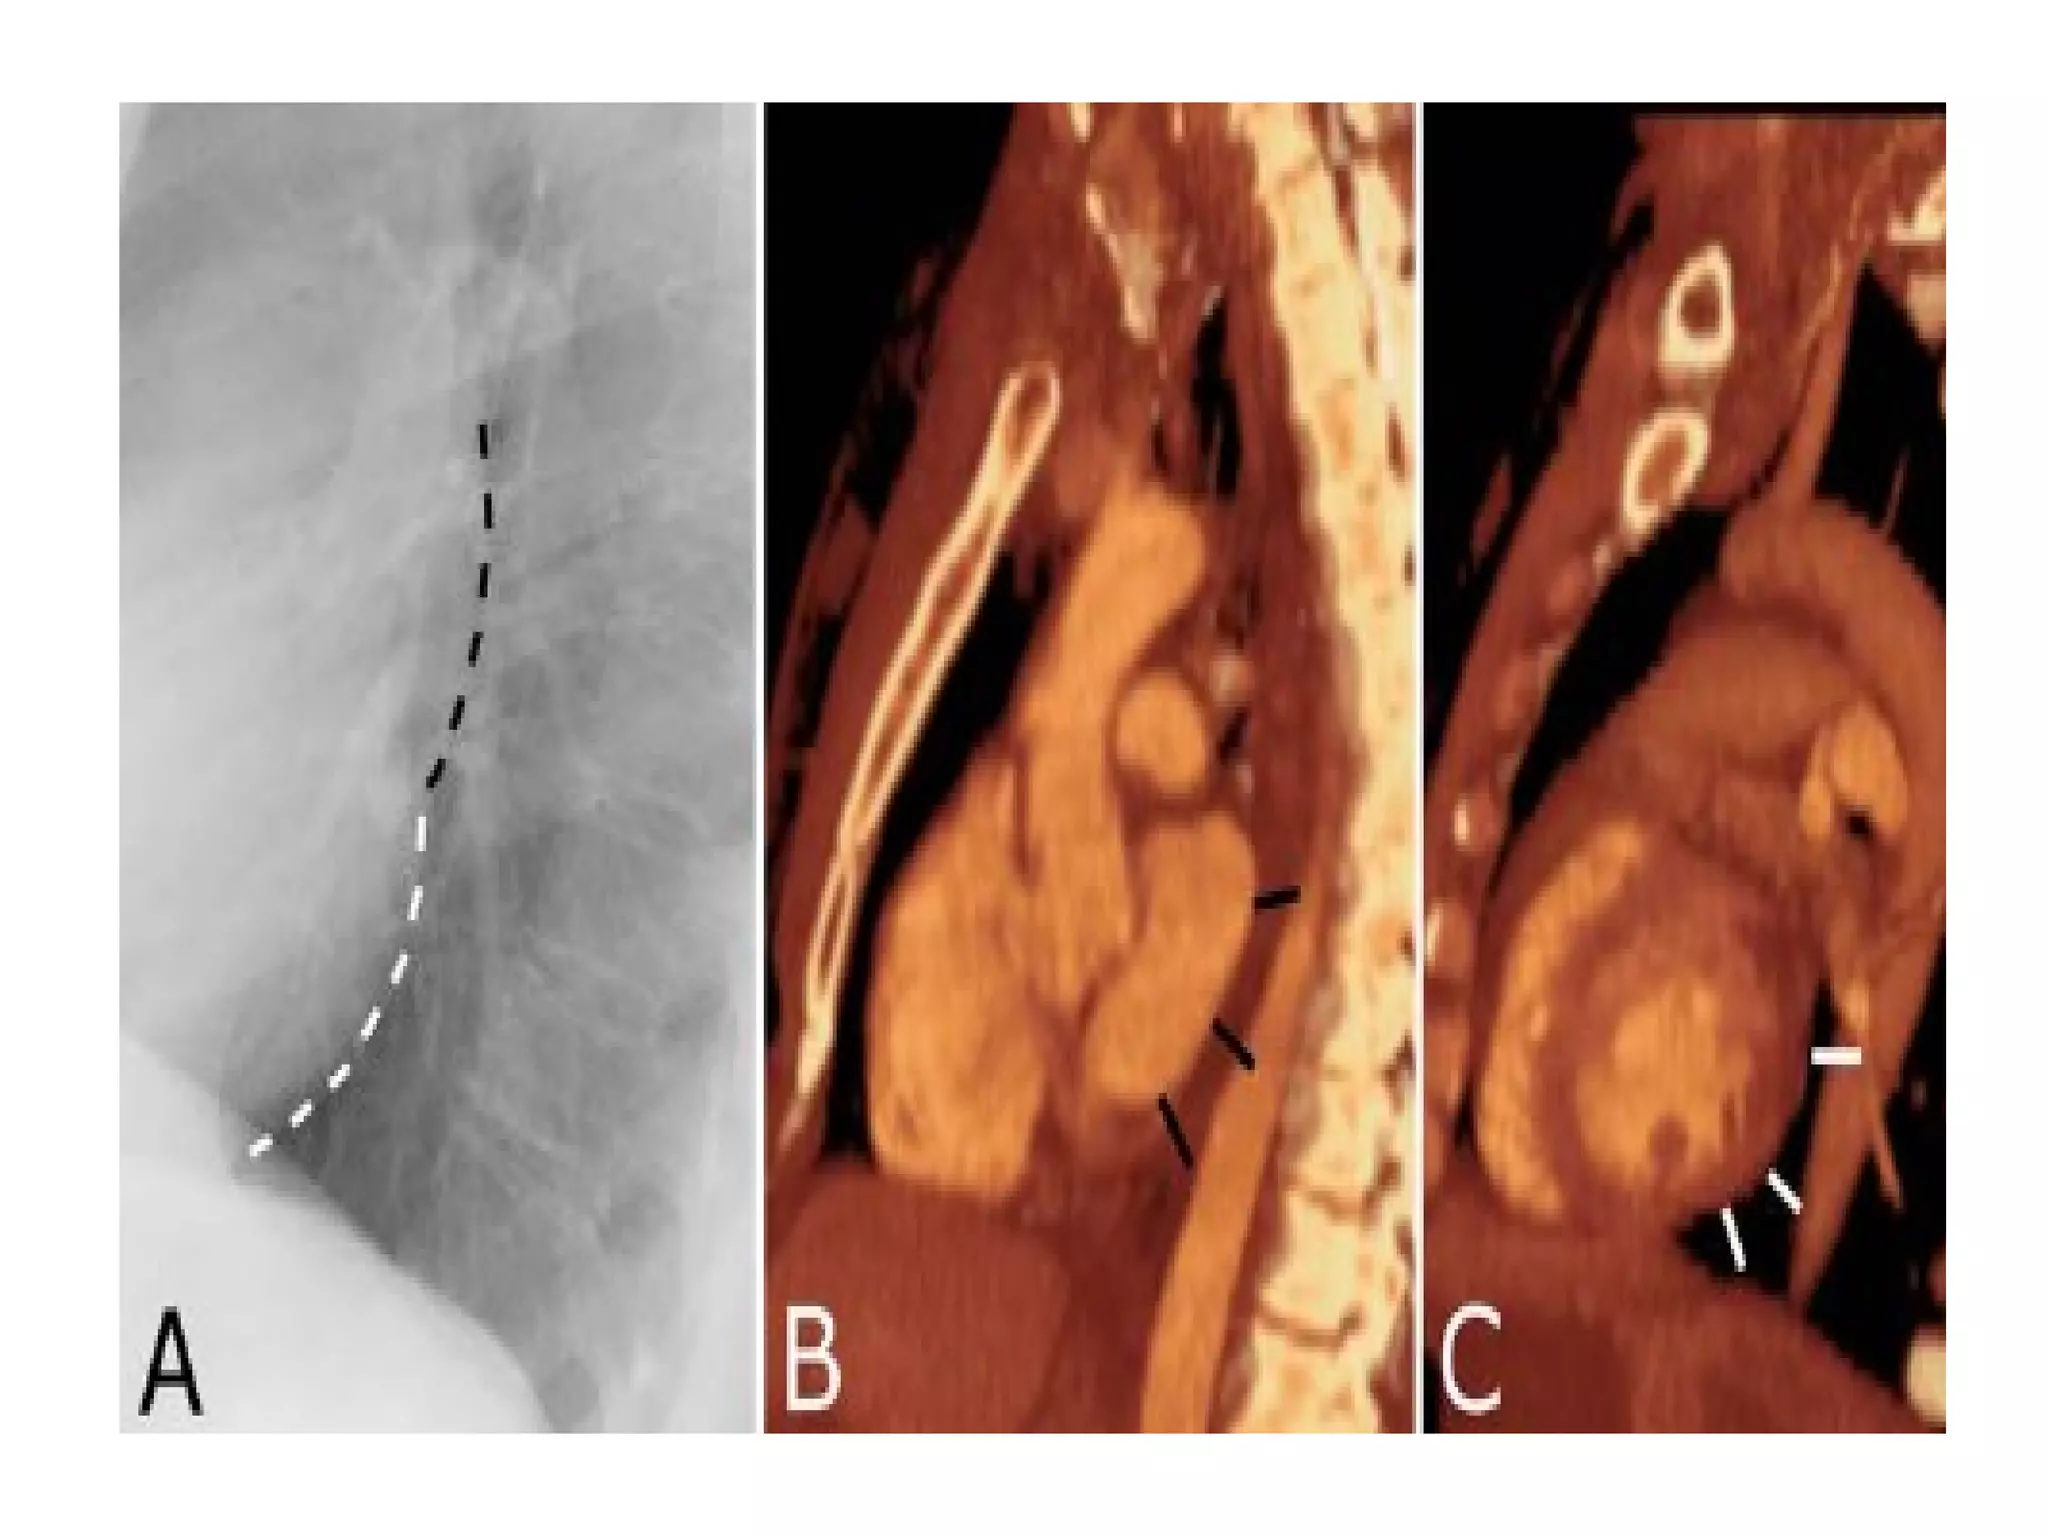

The fissures

The main fissures

The horizontal fissure is seen often incompletely

on PA film

The oblique fissures are seen on lateral film

commence posteriorly at the level of T4 or T5

passing through the hilum. The left is steeper

and finishes 5cm behind the anterior

costophrenic angle, where as the right ends just

behind the angle.

Accessory fissures, the azygos fissure is

comma shaped and nearly always right sided.

The fissures The mainfissures The horizontal fissure is seen often incompletely on PA film The oblique fissures are seen on lateral film commence posteriorly at the level of T4 or T5 passing through the hilum. The left is steeper and finishes 5cm behind the anterior costophrenic angle, where as the right ends just behind the angle. Accessory fissures, the azygos fissure is comma shaped and nearly always right sided.